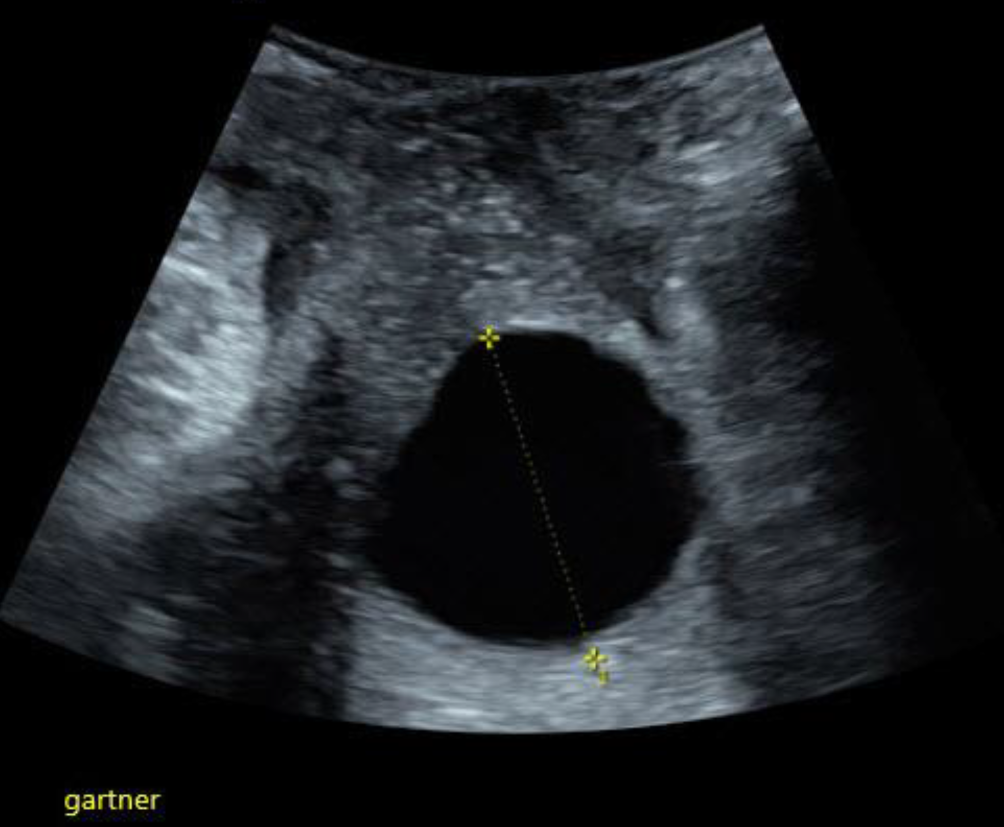

Beckenniere

Beckennieren sind bei Frauen wesentlich häufiger als bei Männern und häufiger auf der linken als auf der rechten Seite. Meist sind sie den Patientinnen bekannt, sie können aber durchaus auch bei einem Vaginalultraschall erstmals auffallen. Da die Rotation der Nieren im Zuge der embryonalen Entwicklung einer Nierendystopie auch gestört ist, liegt das Nierenbecken ventral des Nierenparenchyms und nicht medial. Die Beckenniere sieht also nicht aus wie eine „typische“ Niere im Ultraschall und kann auf den ersten Blick auch für einen soliden Ovarialtumor gehalten werden (Abb. 4). Steht die Diagnose fest, sollte die Gelegenheit genutzt werden, gleich mit 3‑D-Ultraschall nach Uterusfehlbildungen zu fahnden, da diese bei Nierendystopien gehäuft auftreten [1].

Abb. 4

Hier liegt die Beckenniere zwischen Zervix (unten) und Harnblase (rechts im Bild)

Bild vergrößern